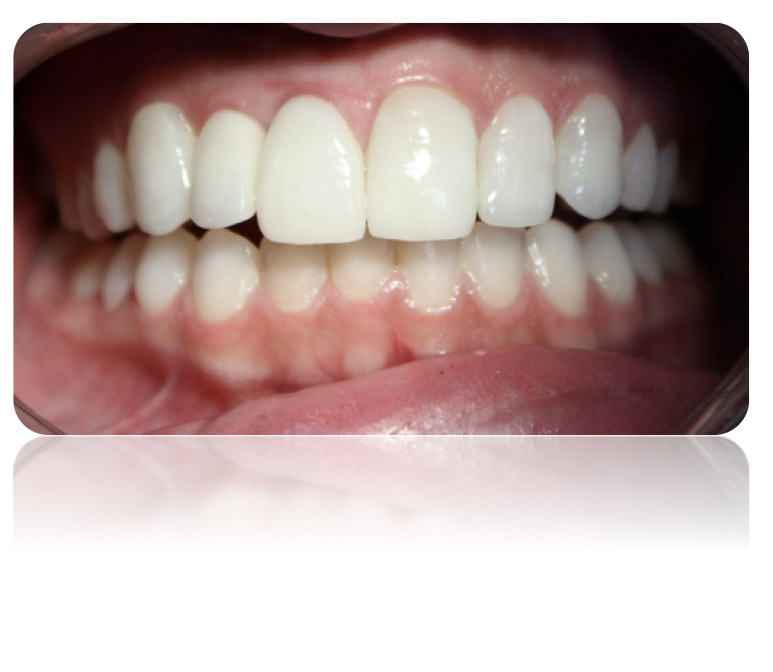

Recupera tu sonrisa

Los implantes son elementos metálicos usualmente en titanio puro que se ubican quirúrgicamente en los huesos maxilares, debajo de las encías. Una vez colocados en el lugar se puede colocar sobre ellos las coronas o puentes fijos que reemplazarán a las piezas dentarias perdidas